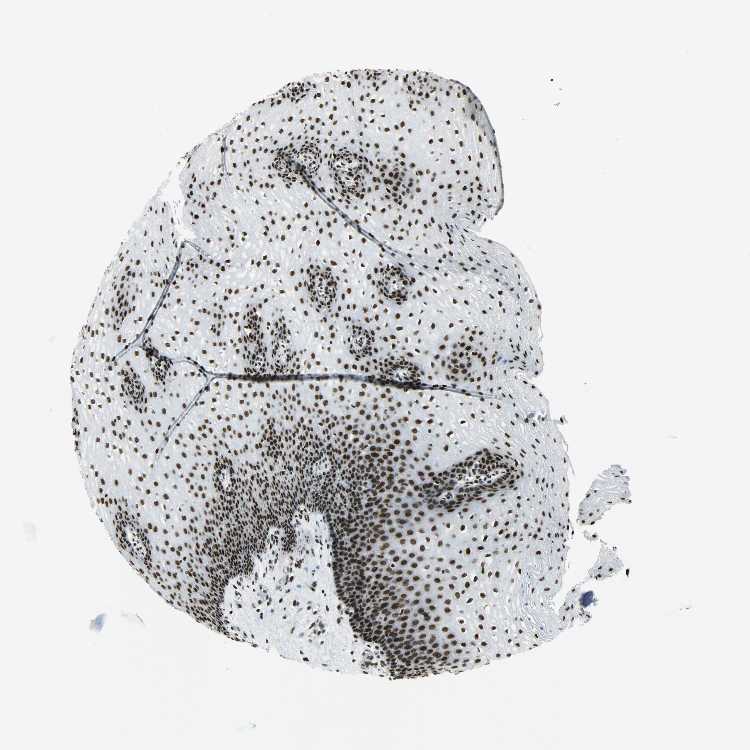

ESOPHAGUS - Antibody stainingi

Antibody staining in the annotated cell types in the current human tissue is reported as not detected, low, medium, or high, based on conventional immunohistochemistry profiling in selected tissues. This score is based on the combination of the staining intensity and fraction of stained cells.

Each image is clickable and will lead to virtual microscopy that enables deeper exploration of all samples and also displays staining intensity scores, fraction scores and subcellular localization as well as patient and tissue information for each sample.

Antibody HPA046440Antibody CAB004652

Squamous epithelial cells MediumHigh